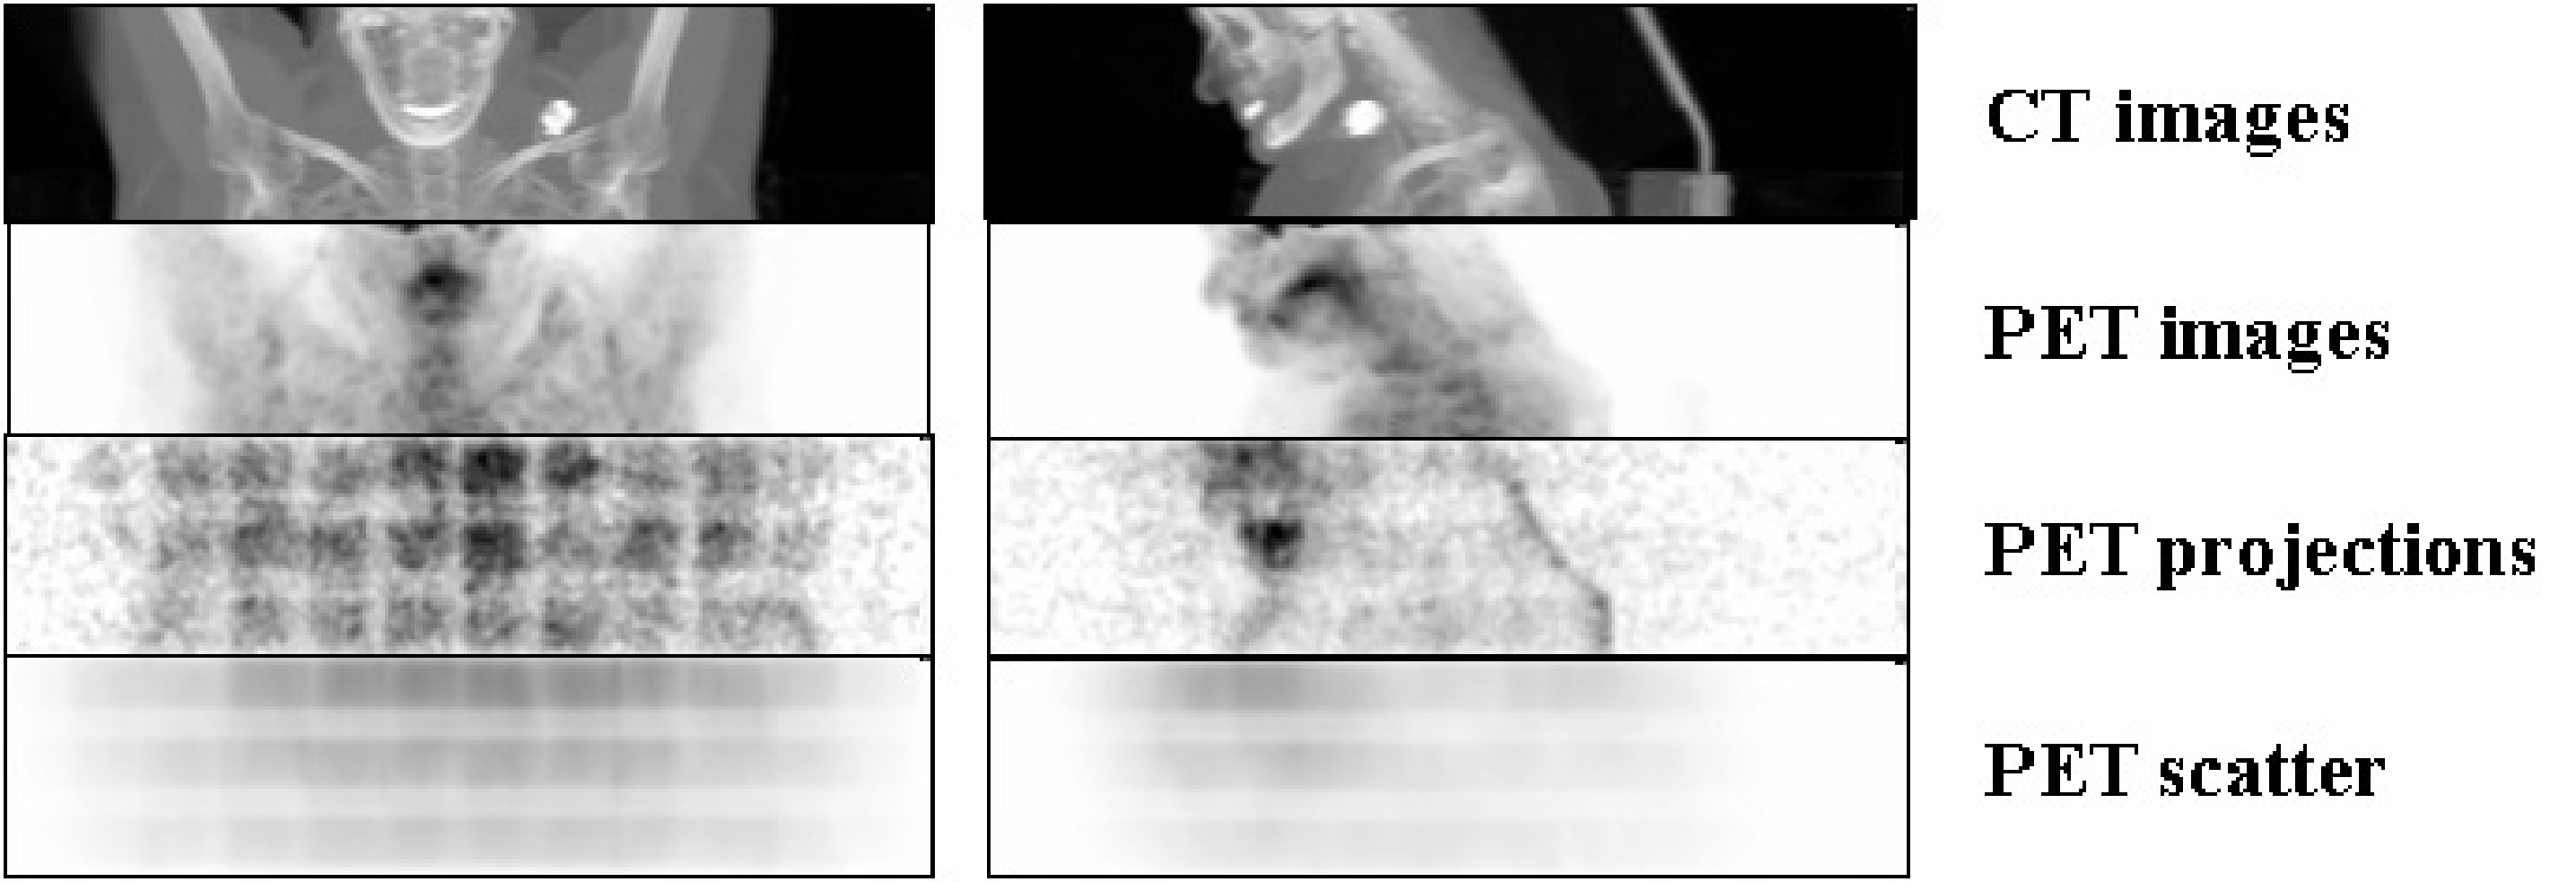

Figure 19:CT and PET images (obtained by maximum intensity projection), and the corresponding raw PET projection data with their estimated scatter contribution. Data were acquired with a Biograph 16 PET/CT system (Siemens). The regular pattern in the raw data is due to sensitivity differences between different detector pairs (see also Figure 23).

Figure 19 gives an example of the original raw PET data from a 3D PET scan (slightly smoothed so you would see something), together with the corresponding estimated scatter contribution (using the same gray scales). Maximum intensity projections of the CT and PET images are shown as well. The regular pattern in the raw PET data is due to position dependent sensitivities of the detector pairs (see also Figure 23). The scatter distribution is smooth, and its amplitude is significant.